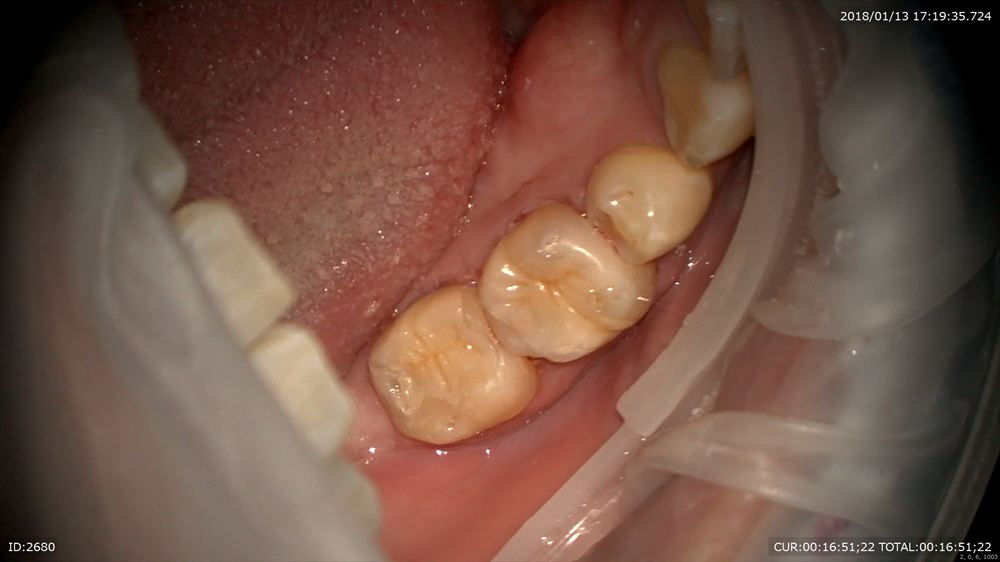

虫歯治療のケース

これを詰めます。

いいですね。レジンでの修復